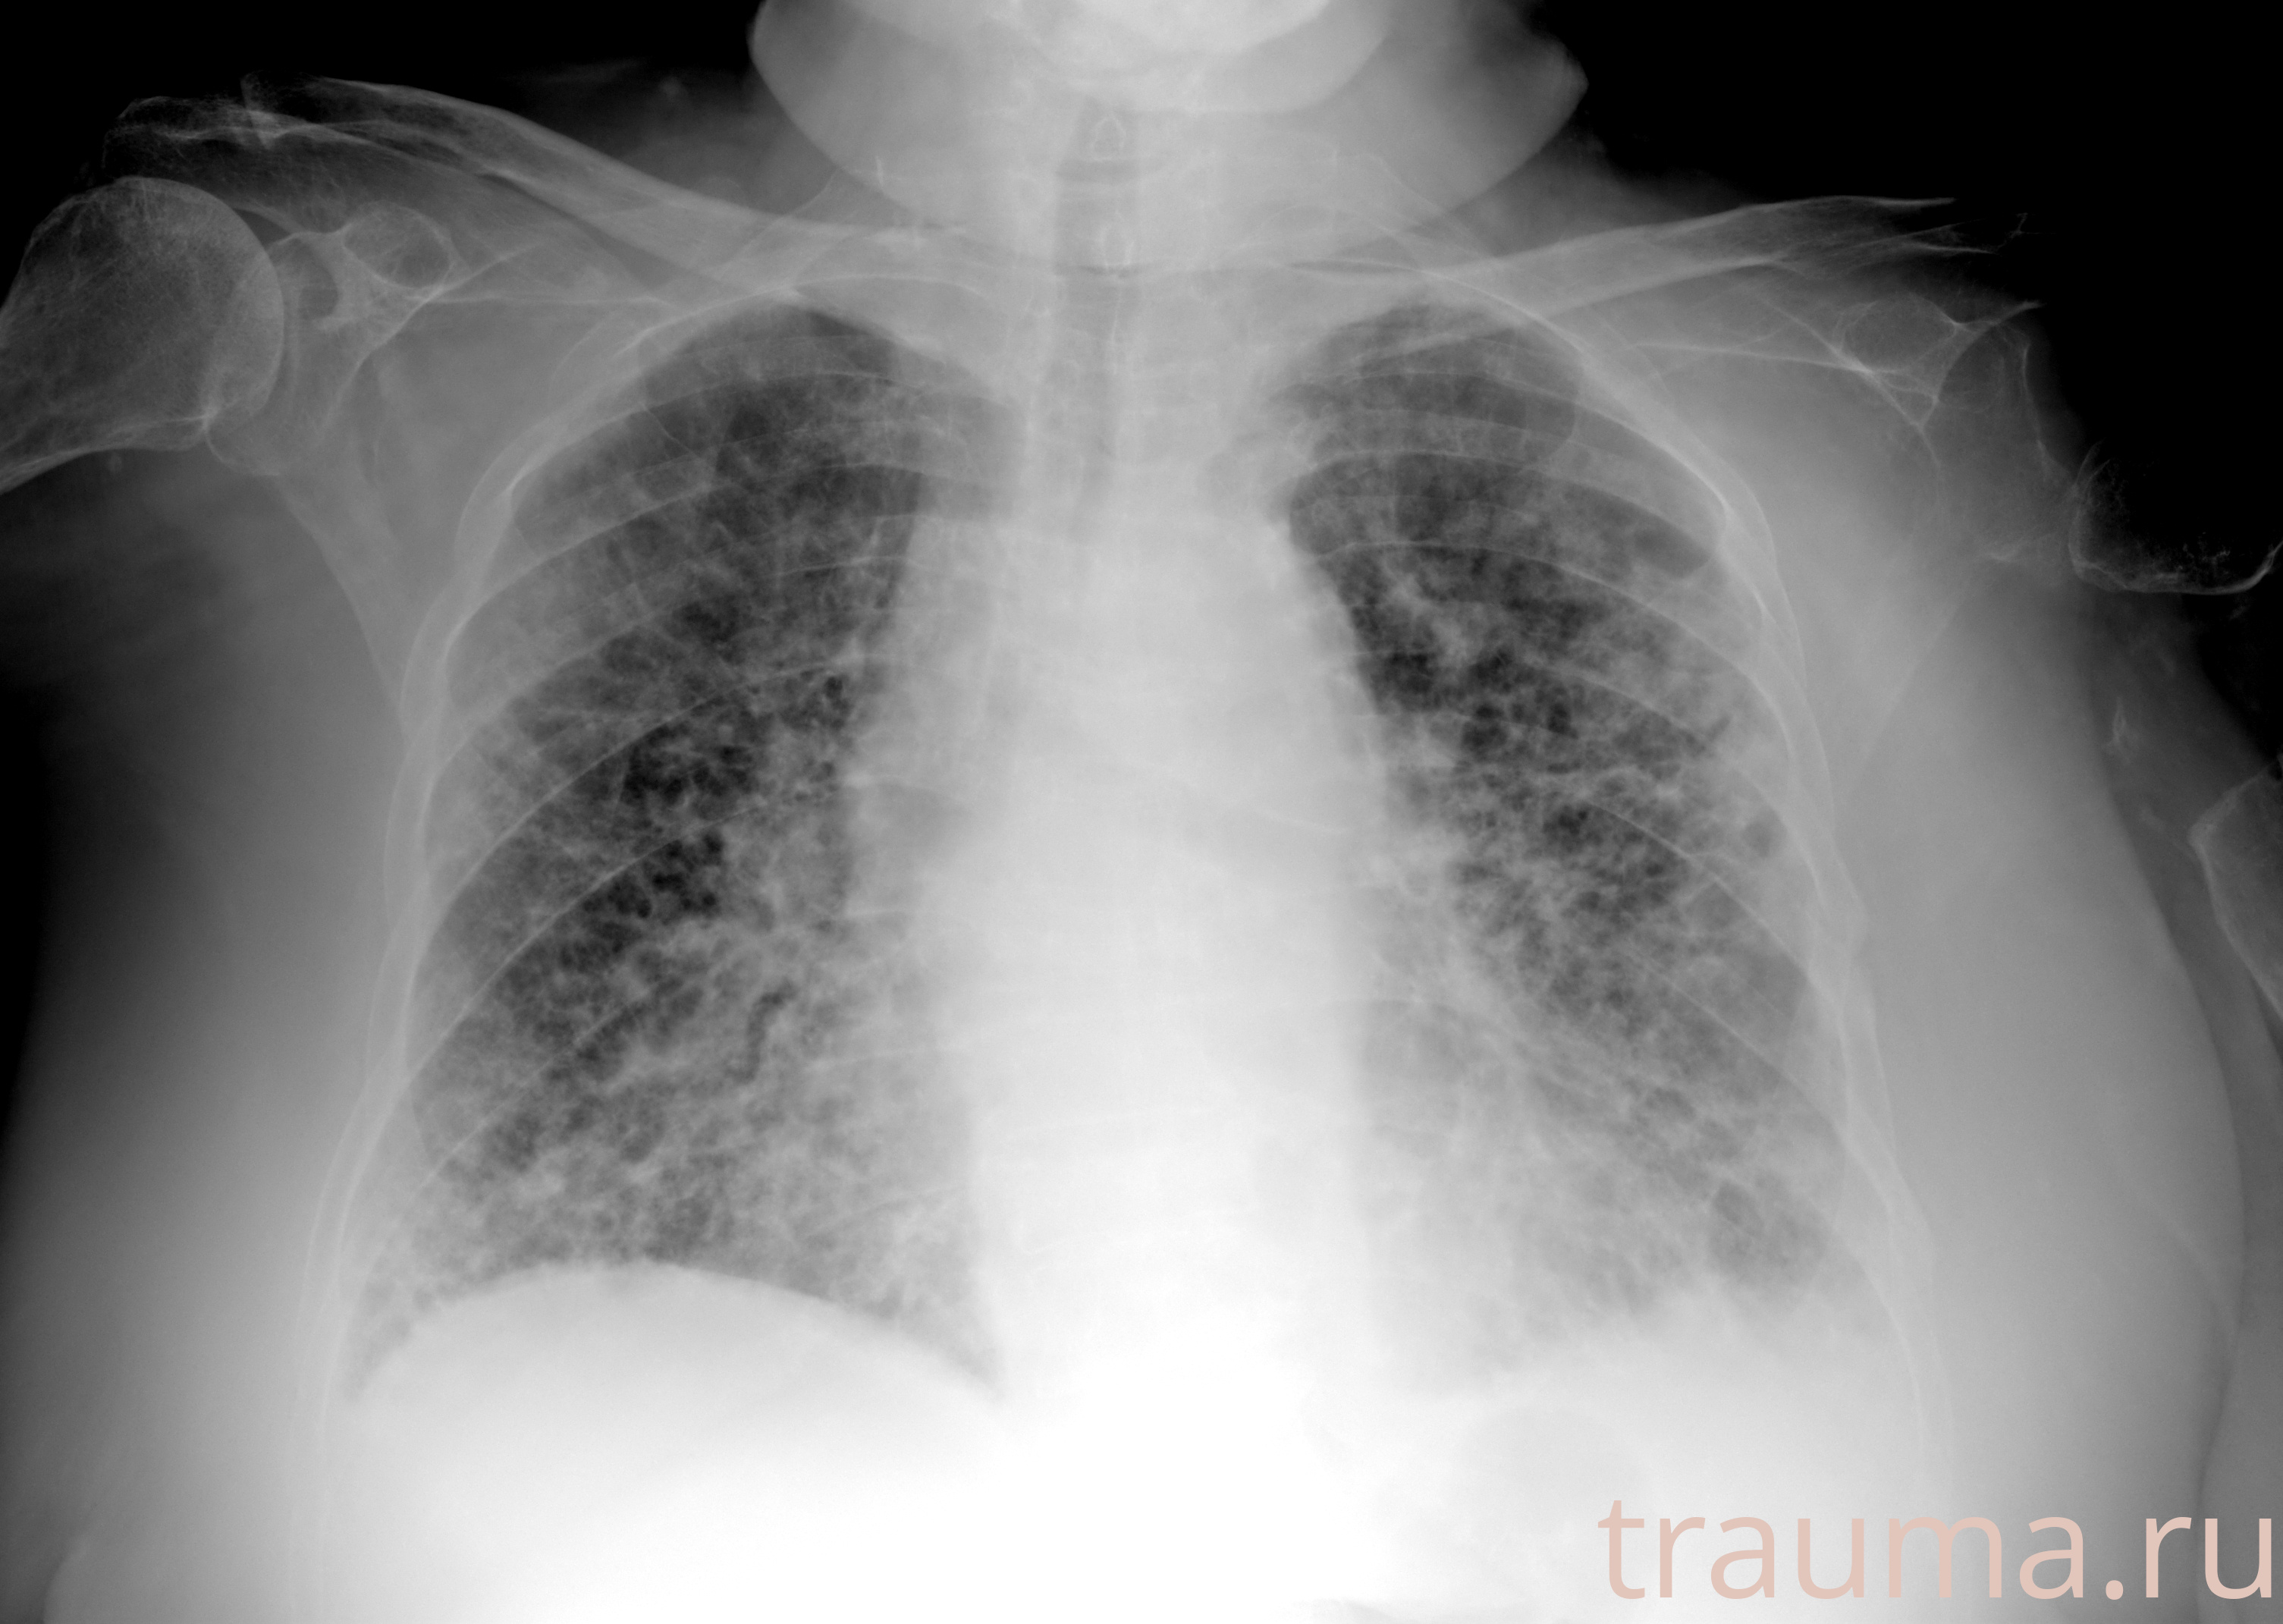

Рентген на дому: по вашему адресу приезжает врач-рентгенолог, травматолог-ортопед с мобильным рентгеновским аппаратом, проводит диагностику травмы или заболевания, делает необходимые рентгенограммы, дает рекомендации по дальнейшему лечению. Получить качественные снимки в домашних условиях возможно благодаря уникальной методике, разработанной МосРентген Центром для института  Склифосовского

при переломе шейки бедра и пневмонии от компании МосРентген Центр - партнера Института имени Склифосовского